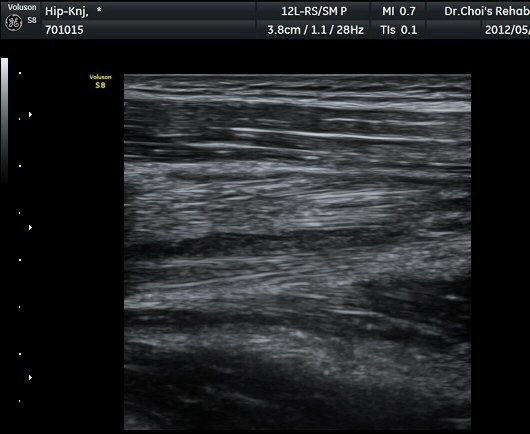

Á¤»óÀûÀÎ ±ÙÀ°ÀÇ ¸ð¾çÀÌ ¼Ò½ÇµÇ°í Àú¿¡ÄÚ º´º¯À¸·Î °üÂûµÈ´Ù(±×¸² 6). ŽÃËÀÚ¸¦ Á¶±Ý ¸»´ÜÀ¸·Î

À̵¿ÇÏ´Ï Àú¿¡ÄÚ º´º¯³»¿¡¼­ ±¹¼ÒÀûÀÎ ¼ö¾×Àú·ù°¡ °üÂûµÈ´Ù(±×¸² 7, 8).  À̵ιڱ٠ÀåµÎ Á¾´Ü¸é